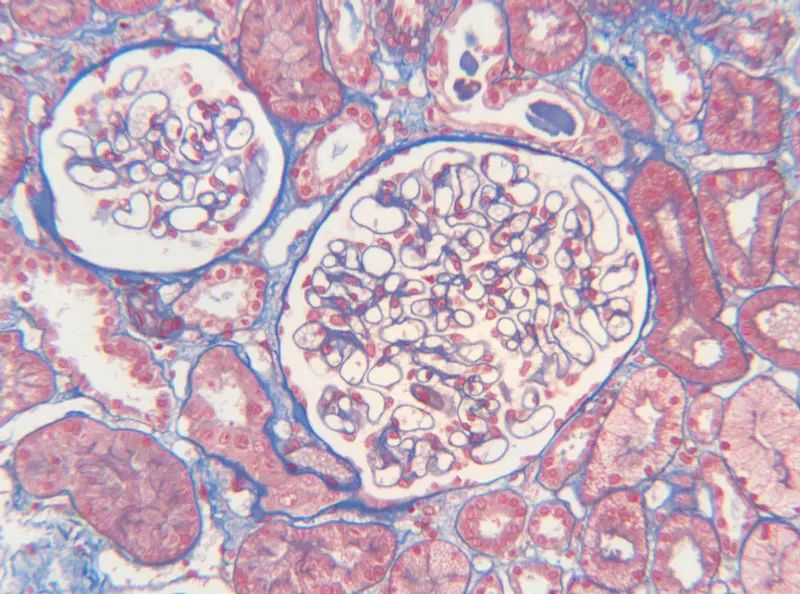

首先,讓我們深入探討MASSON染色的原理。MASSON染色的原理與陰離子染料分子的大小和組織的滲透性密切相關(guān)。染料的分子量決定了其穿透組織的能力:小分子量的染料更容易穿透結(jié)構(gòu)致密、滲透性較低的組織,而大分子量的染料則更傾向于進入結(jié)構(gòu)疏松、滲透性較高的組織。在MASSON染色中,由于肌纖維間隙較小,而膠原纖維間隙較大,因此小分子量的麗春紅染料更容易滲透進入肌纖維并使其呈現(xiàn)紅色,而大分子量的苯胺藍染料則主要進入膠原纖維并使其呈現(xiàn)藍色或綠色。

MASSON染色的陽性意義在于,它能夠幫助研究人員區(qū)分膠原纖維和肌纖維,從而觀察病變組織中纖維結(jié)締組織的增生和分布。當(dāng)MASSON染色結(jié)果呈現(xiàn)陽性時,通常意味著局部組織中存在膠原纖維的增生。這種增生可能是由于局部皮膚出現(xiàn)炎癥或組織增生等病理 過程所導(dǎo)致的。因此,MASSON染色的陽性結(jié)果可以作為判斷組織纖維化程度的一個重要指標(biāo)。